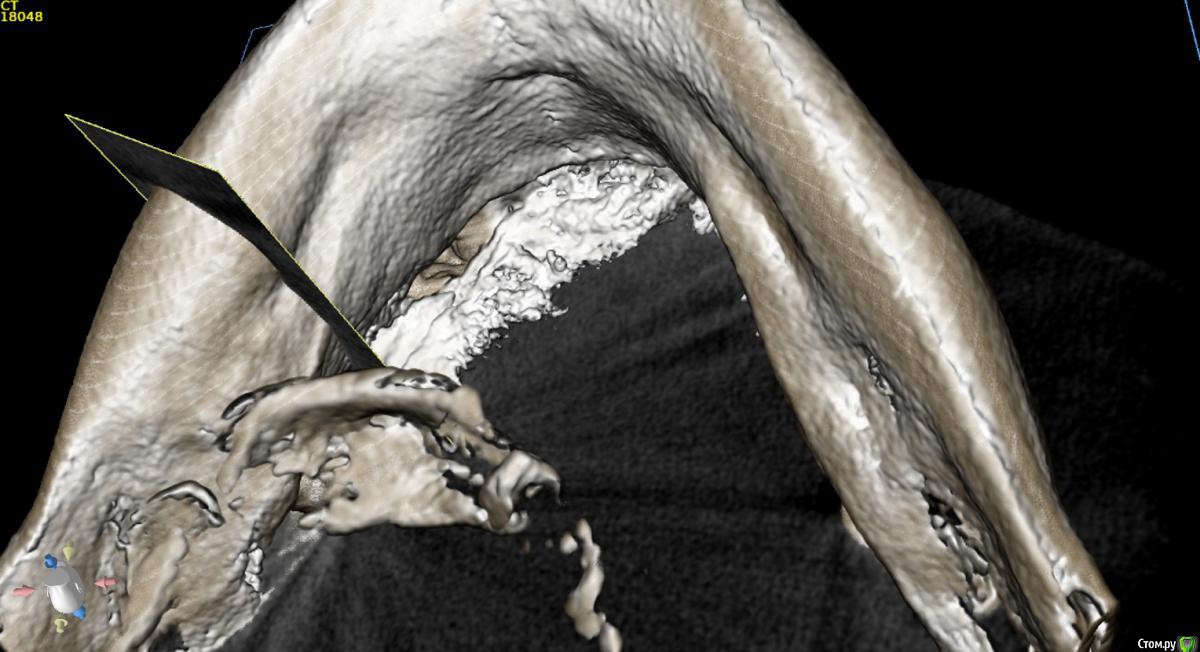

Борис80 Опубликовано 23 мая, 2018 Автор Поделиться Опубликовано 23 мая, 2018 какое то образование с четкими границами, достаточно большое, по структуре напоминает кость, но имеет четкий контур...в пределах челюсти, жалоб не предъявляет, с правой стороны(шрам на шее) была резекция подчелюстной слюнной железы, 3д моделировка снаружи: Ссылка на комментарий

Борис80 Опубликовано 23 мая, 2018 Автор Поделиться Опубликовано 23 мая, 2018 были бы более скромные размеры, я бы принял подобное за секвестры, но тут 3 см... Ссылка на комментарий